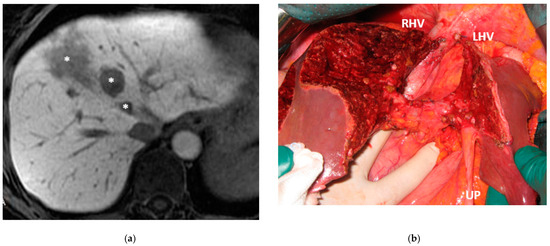

Figure 4. Intraoperative field images of a vessel-guided mesohepatectomy of S1/S4 en-bloc with MHV for liver partition (MLP). MLP is a minor resection (less than 3 adjacent liver segments) inducing a major hepatic scaffold modification transforming the liver into a paired organ. (a) Liver transection lines (yellow dotted lines). (b) Intraoperative view of the two livers. (c) Surgical specimen of S4/S1 en-bloc with MHV corresponding to a volume of 205 mL. Abbreviations: MLP: mesohepatectomy for liver partition; MHV: middle hepatic vein; RHV: right hepatic vein; S: segment; GP: glissonean pedicle; UP: umbilical portion.